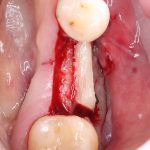

Для получения костного блока мы использовали ультразвуковую пьезохирургическую систему. Это самый удобный и безопасный инструмент для проведения подобных манипуляций. С помощью него мы сформировали и выделили костный блок. Он должен отделяться легким движением остеотома или элеватора. Как это сделать правильно — читай здесь>>

Кстати, если костный блок не отделяется от костного ложа легким движением элеватора, значит он неправильно сформирован или не до конца выделен. Вообще, любое чрезмерное усилие в хирургии — это всегда следствие рукожопия. Если тебе что-то приходится делать с усилием (установка имплантата, удаление зуба и т. д.) — значит ты делаешь это неправильно. Остановись и подумай, что именно.

Я зафиксировал костный блок практически без адаптации на несколько винтов. Обрати внимание, что винты находятся в зоне, где не планируется установка имплантатов. Фиксация должна быть надежной, поскольку мне еще предстояла подготовка лунок для имплантатов. Трех винтов для этого вполне достаточно.

Дальнейшая адаптация костного блока свелась к сглаживанию острых краев. После чего я приступил к подготовке лунок и установке имплантатов.